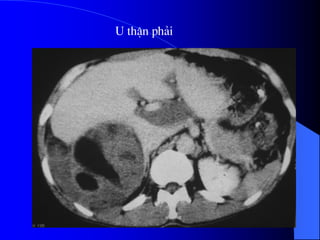

4.1. U nhu mä tháûn - Carcinome tãú baìo tháûn

Ung thæ tháûn chiãúm 3% ung thæ caïc loaûi åí

ngæåìi låïn, 95% trãn 50 tuäøi, nam gáúp âäi næî.

Yãúu täú thuáûn låüi laì tháûn âa nang, suy tháûn kãút

håüp âa nang màõc phaíi, tháûn dë daûng hçnh

moïng ngæûa, nghiãûn thuäúc laï.

- Siãu ám phán biãût âæåüc khäúi âàûc vaì dëch.

Nãúu laì khäúi âàûc seî xem xeït cáúu truïc ám, coï thãø

giaím, âäöng hoàûc tàng ám, xem âäü âäöng nháút ám,

väi hoïa.

Nãúu laì khäúi dëch, seî tçm täø chæïc âàûc hoàûc vaïch

trong nang.

Siãu ám coï thãø tháúy haûch di càn, xám láún ténh

maûch.

Noïi chung khi phaït hiãûn khäúi âàûc trãn siãu ám,

cáön chuûp CLVT âãø âaïnh giaï roî hån baín cháút, sæû

xám láún, di càn.

- CLVT phán biãût khäúi âàûc hay dëch, phaït hiãûn

väi hoïa nhoí, xuáút huyãút trong u, tçnh traûng

tæåïi maïu cuía u.

Pháön låïn træåìng håüp phán biãût âæåüc u laình vaì

u aïc.

Xem xeït âæåìng dáùn niãûu bë giaîn, bë xám láún.

CLVT kiãøm tra di càn haûch xám láún vuìng

xung quanh, xám láún maûch maïu, di càn xa,

cå såí âãø phán giai âoaûn tiãún triãøn u, cáön

thiãút cho phæång phaïp âiãöu trë.